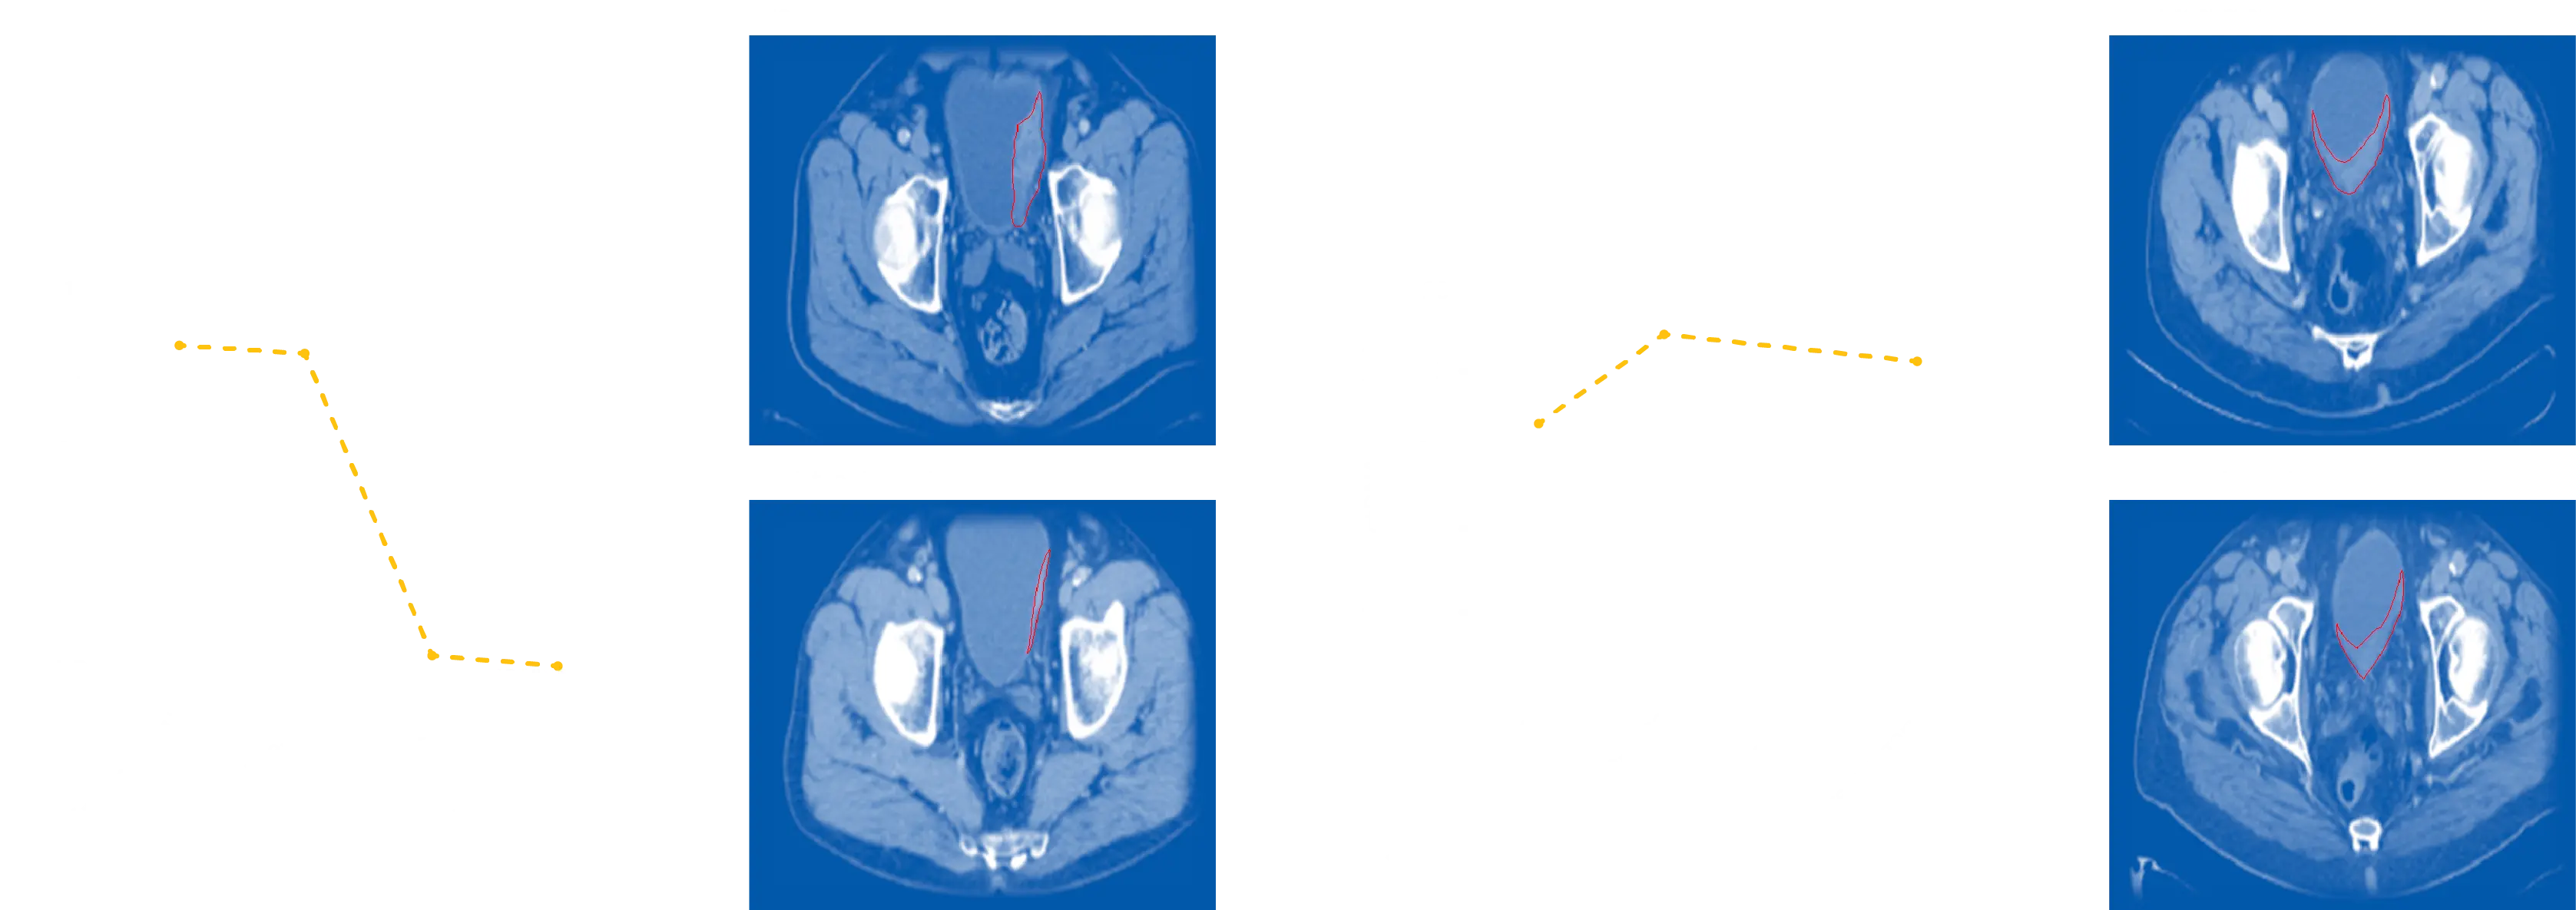

*image adapted from van Dorp J et al. High- or low-dose preoperative ipilimumab plus nivolumab in stage III urothelial cancer: the phase 1B NABUCCO trial. Nat Med. 2023 Mar;29(3):588-592. doi: 10.1038/s41591-022-02199-y. Epub 2023 Feb 2. Erratum in: Nat Med. 2024 Jan;30(1):304.